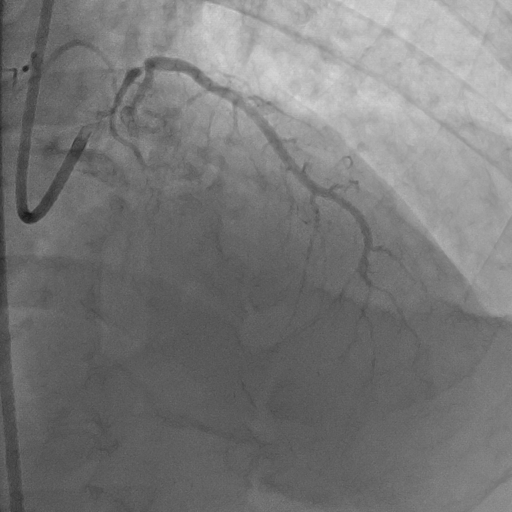

Hình ảnh: động mạch chủ trước khi phẩu thuật

Kết quả chụp mạch vành cho thấy mạch vành của bệnh nhân bị tắc hoàn toàn từ vị trí xuất phát của nhánh liên thất trước động mạch vành trái, trong khi đó nhánh động mạch mũ của động mạch vành trái và nhánh động mạch vành phải vẫn hoạt động bình thường.